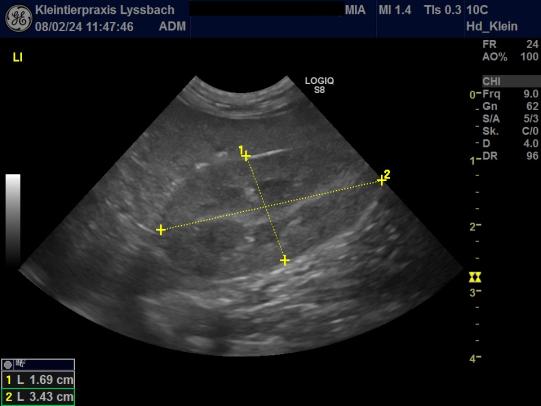

Zur genaueren Abklärung wird nun ein Bauchultraschall durchgeführt. Die Nieren erscheinen in Grösse und Form recht unauffällig, sie sind im Ultraschall aber etwas echogener ("heller") als üblich und der Übergang von Rinde zu Mark ist etwas verwischt. Diese Befunde sind nicht beweisend für ein Nierenproblem, weshalb wir eine weitere Urinprobe gekühlt und per Kurier in ein externes Labor zur weiteren Untersuchung einschicken.